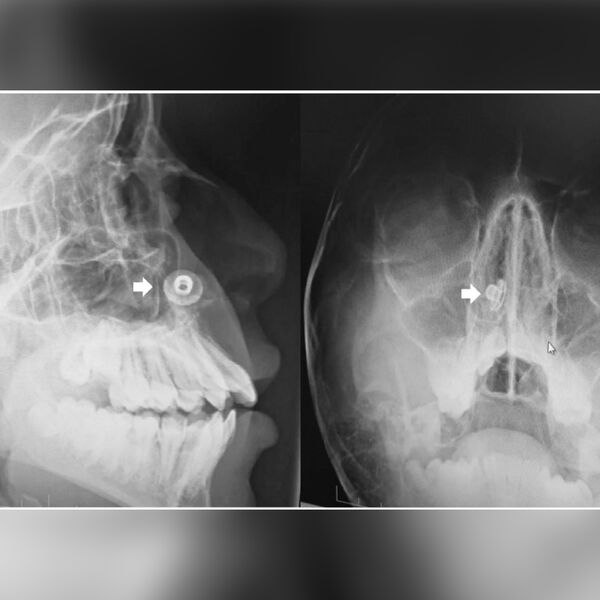

В носу 17-летнего подростка из Великобритании нашли металлическую пуговицу, которая находилась там 10 лет. Как сообщает Need To Know,

Недавно юноша пришел на плановую рентгенографию зубов, и во время процедуры медики обнаружили в нижней части его носовой полости инородный предмет. Подросток был потрясен, узнав об этом, и отрицал, что в детстве у него что-либо застревало в носу. Однако родители мальчика вспомнили, что обращались за медицинской помощью в связи с подозрением на инородное тело в носу, когда их сыну было семь лет.

Врачи объяснили отсутствие у пациента каких-либо симптомов, включая неприятный запах и насморк, удачным расположением пуговицы. В итоге ее удалили под местной анестезией, пока юноша находился в полусидячем положении, чтобы снизить риск смещения в дыхательные пути, добавили медики. После операции подростку прописали раствор, способствующий процессу заживления. За две недели он полностью восстановился и заявил, что чувствует себя хорошо.